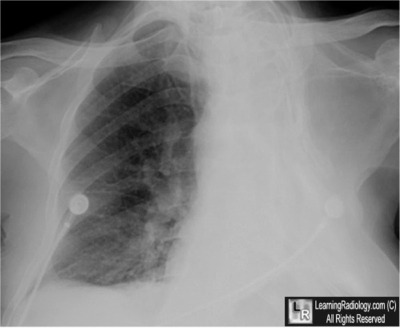

Case of the Week 508

What is the most likely diagnosis?

• 85 year-old male with shortness of breath

Frontal Chest Radiograph

5. Thoracoplasty for TB

Thoracoplasty for TB

·         Defined as a “remodeling or reshaping of the thorax; especially, the operation of removing the ribs, so as to obliterate the pleural cavity in cases of empyema”

·         Thoracoplasty was used from the early 1900’s through the late 1950’s as one of the more permanent forms of collapse therapy for TB

o       Frequently used as a last resort in gravely ill patients

·         Collapse therapy was based, at least in part, on the observation that healed tuberculous cavities were closed and not open

o       The therapies were directed towards closing the cavities